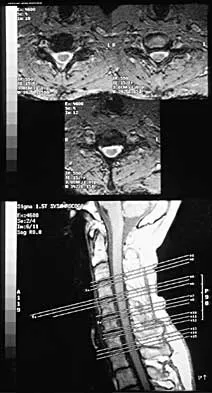

A patient who has had neck pain radiating down the arm for the past 4 weeks reports that the pain was excruciating during the first week. Management consisting of anti-inflammatory drugs and physical therapy has decreased the neck and arm symptoms from 10/10 to 3/10. He remains neurologically intact. MRI and CT scans are shown in Figures 5a and 5b. The best course of action should be

Explanation

Although the patient has a large herniated nucleus pulposus, the pain has decreased from 10/10 to 3/10 over a 4-week period and the patient is now free of any neurologic symptoms. It is quite likely that further nonsurgical management will continue to resolve his symptoms. In the absence of any neurologic deficits, there is no evidence that the patient is at significant risk for paralysis. Saal JS, Saal JA, Yurth EF: Nonoperative management of herniated cervical intervertebral disc with radiculopathy. Spine 1996;21:1877-1883.